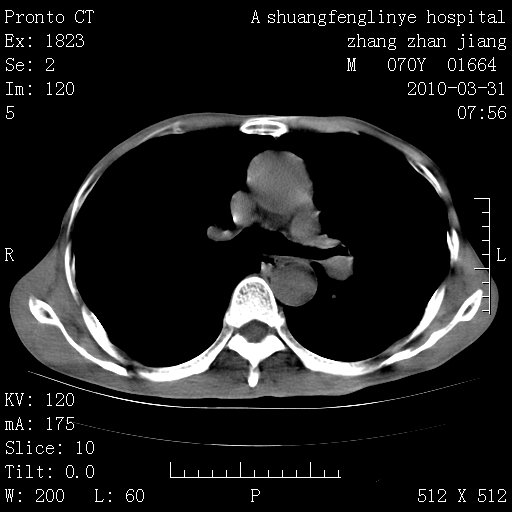

双上肺继发型tb并左上空洞形成,主动脉冠脉钙化。

1)两肺上叶继发性肺结核并左肺上叶空洞形成。2)冠状动脉及主动脉钙化。